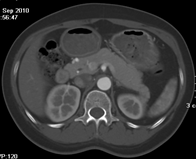

目前臨床對于16層CT的認可主要集中在三維成像領域上的突破.在16層CT的產品平臺上,常規(guī)掃描就能實現(xiàn)滿足三維成像的要求,因此16層也被稱為三維CT,三維成像給臨床診斷帶來了更精確更豐富的診斷信息,我們以臨床為例:

如上圖所示,相鄰的三張軸位圖像未見明顯異常,根據(jù)傳統(tǒng)軸位圖像很難得到準確的臨床診斷。

同一病人利用容積數(shù)據(jù)進行三維處理后,高品質MPR和三維圖像上則清晰顯示了縱向排列的腹腔干與腸系膜上動脈相鄰近,血管發(fā)生變 異,近端血管閉塞,為臨床提供了精確的診斷信息。

從上面的例子可以看到,能否為臨床提供高品質的三維影像成為了16層CT的核心價值,而東芝新一代的 全景三維16層CT擁有最為  先進的3項核心技術,在16層核心價值上的表現(xiàn)自然值得期待。